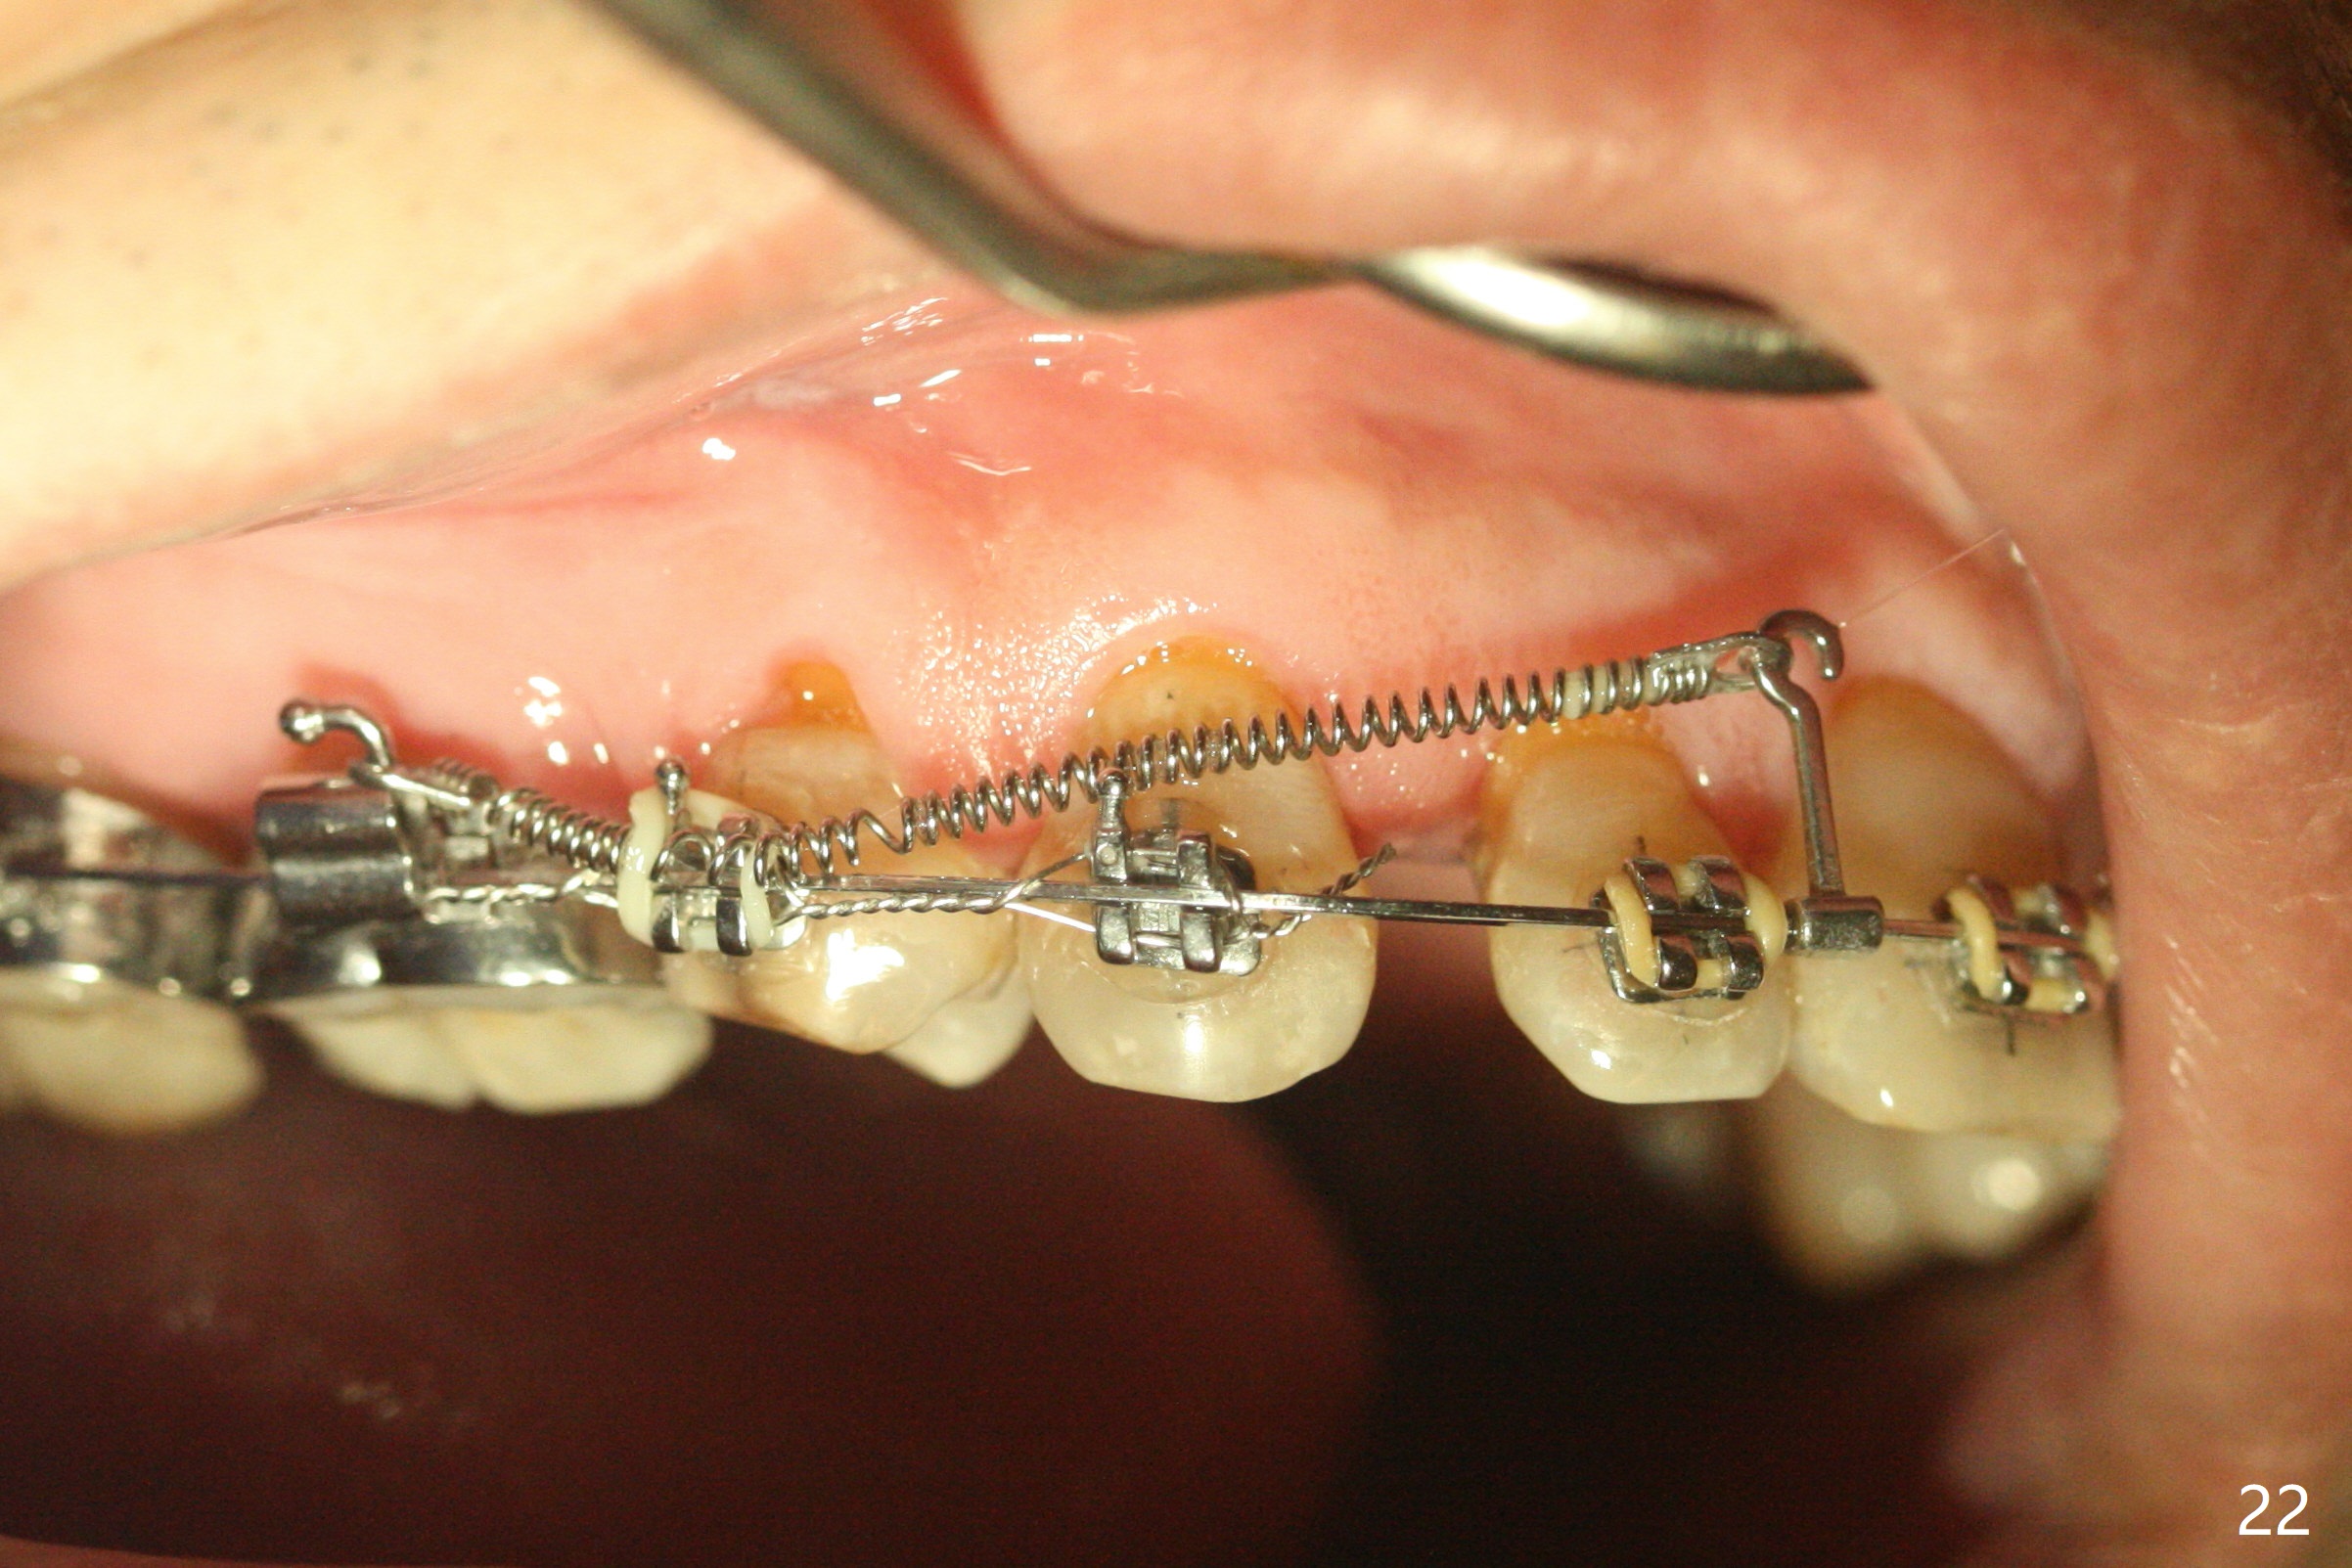

A 40-year-old man requests orthodontics after #17 and 32 extraction. UL5 is missing (Fig.1), while the upper midline deviates to the left (Fig.2 arrow) with crowding between UL2 and 3 (Fig.3). The main goal is to retract UL5 distal and move the upper midline to the right to alleviate UL anterior crowding. Implant will be not needed. To monitor potential root resorption associated with tooth movement, preop PAs are taken (Fig.4-7). The space for an implant at UR5 is narrow. UR4 needs to be distalized using UR7 or a miniimplant distal to UR7 as an anchor (Fig.8). UR4 and 3 will be repositioned to establish Class I occlusion (Fig.9). The space gained by UR4 distalization may be enough to correct the upper midline deviation and UL3 malposition (Fig.10). Brackets will be placed in the lower arch in spite of the normal alignment (Fig.11). UL2 and 3 brackets are unable to be engaged to 14 niti wire (Fig.12). Next visit try to engage UL2 bracket. If not, save the old wire for possible future reuse. Closed spring is placed with 18 ss wire <3 months post banding (coronavirus). Three weeks post closed spring between UR4-7, UR3,4 are being distalized (Fig.13). Distalization of UR4 is not much in 5.5 months (Fig.14,15). It seems necessary to use a miniimplant distal to UR7 as an anchor (Fig.16 white circle), place a long hook mesial to UL4 (more or less root movement instead of tilt) and place the same closed spring between the anchor and hook. In spite of the fact that UR4 seems to have been completely distalized and that UR2 is being distalized 8 months post banding (Fig.18), a 8 mm long mini-implant is placed in the maxillary tuberosity with minimal local anesthetic (Fig.17,19). A longer closed spring (18 mm) is placed between the implant and UR3 hook (Fig.20). Next appointment a lingual button will be placed at UR4 for rotation, while a post hook mesial to UR3 for torque. UR3 distalizes with the help of UR mini-implant, which is unfortunately loose. Next visit place lingual button at UR4 (Fig.21 arrow) to distalize the lingual cusp. Crimpable power hook is placed mesial to UR2 for distalization (for root torque, Fig.22). If it works, remove the wire and reposition the hook for UR1 next visit. UR2 is distalized in one appointment (~ 1 month, Fig.23, as compared to Fig.22). With lingual button at UR4, rotation seems to have been corrected shortly (Fig.24 arrow).